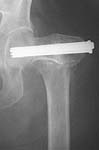

Does anyone on the list know of any references regarding the placement of cannulated hip screws above/below the lesser trochanter as it relates to the risk of subsequent subtroch fracture? i know placement should be above the lesser trochanter but i have been unable to find evidence to support this. thank you.

Reported 20% incidence of fracture if screws are placed too low, below the lesser trochanter, or  with un-filled drill holes there too. I have not looked at it in a long time but I believe the reference on this topic is: Karr, Clin Ortho Rel Res 1985.